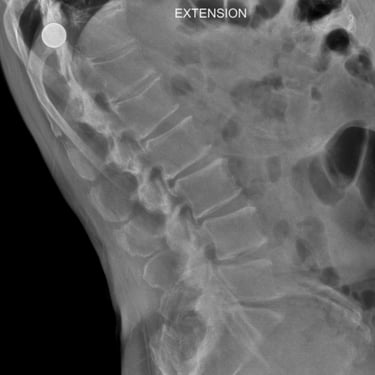

La listesis L4–L5 asociada a estenosis lumbar severa se caracteriza por el deslizamiento vertebral y el estrechamiento del canal espinal, generando dolor lumbar, claudicación neurogénica y compromiso radicular. Cuando el tratamiento conservador no logra un control adecuado de los síntomas, la fijación transpedicular (FTP) asociada a la fusión intersomática transforaminal (TLIF) constituye una alternativa quirúrgica eficaz. Este procedimiento permite descomprimir las estructuras nerviosas, restaurar la alineación vertebral y proporcionar una estabilización sólida del segmento afectado, favoreciendo una recuperación funcional segura y una mejor calidad de vida.